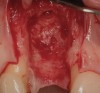

Figure 16  (Case 2) Defect grafted with mineralized freeze-dried bone allograft.

Figure 17  (Case 2) Long-term resorbable membrane in place with autogenous connective tissue.